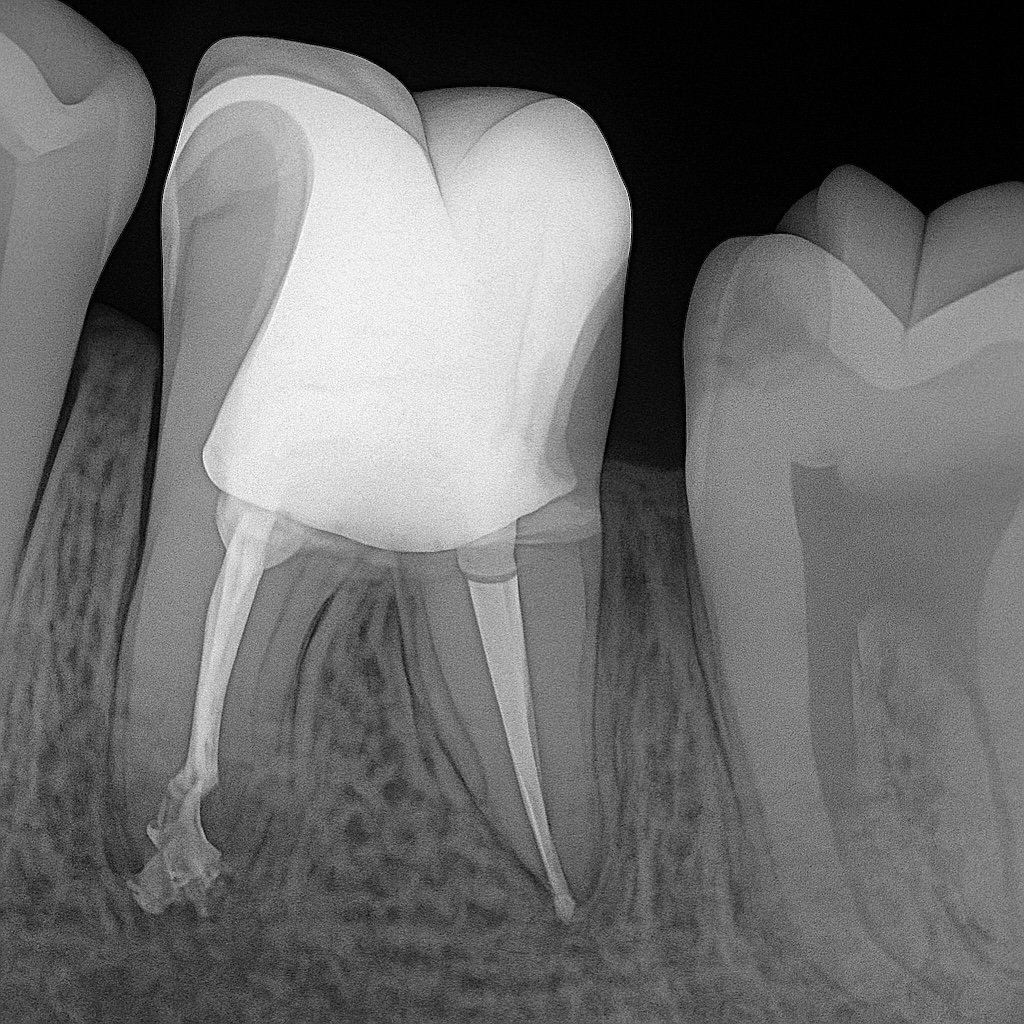

B. Endodontic Therapy

Performed under high magnification for accuracy:

Protocol

- Glide path established

- Canals shaped with NiTi rotary instrumentation

- Irrigation: NaOCl + EDTA protocol

- Canals dried and obturated with bioceramic sealer + GP single cone

(chosen for its bioactivity, dimensional stability, and superior sealing)

Coronal Seal

- Immediate bulk-fill flowable dentin replacement to block microleakage

- This step is strongly supported in the literature for long-term success

✔ Radiographs confirm complete obturation and dense coronal seal